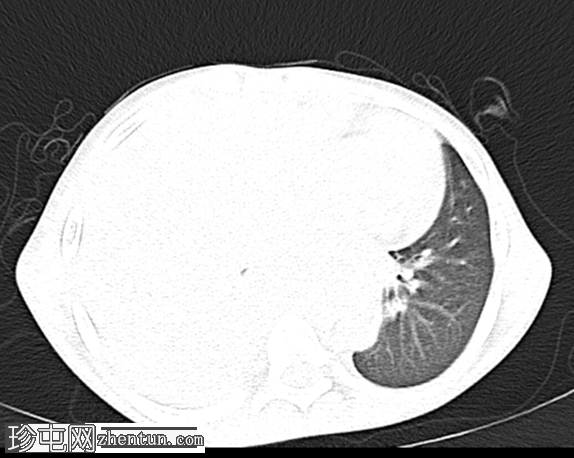

定位扫描图像发现:

右肺野完全影,伴有轻度向对侧(左侧)纵隔移位,提示大量胸腔积液或大型占位性病变。